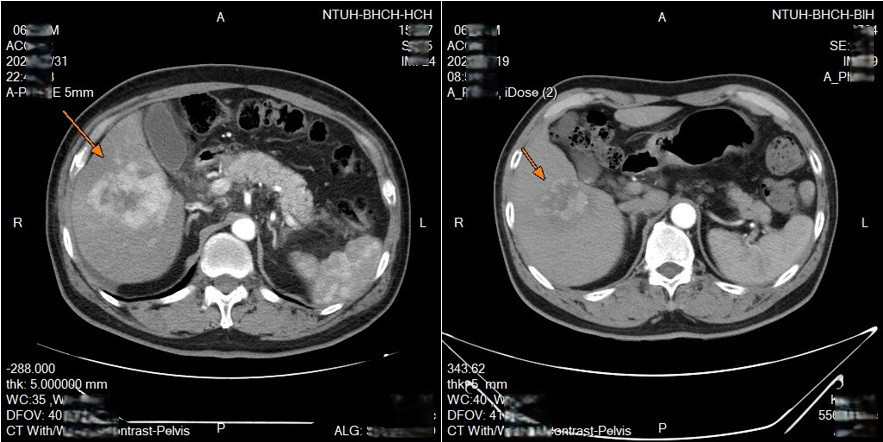

新竹臺大分院收治一名63歲男性,先是得了淋巴癌,而後在治療期間又發現肝腫瘤,確診肝癌。經醫療團隊與病人充分討論後,安排進行鎖骨下導管置放於肝動脈灌注化療,歷經兩次療程腫瘤明顯縮小。

透過可移動式的導管放置,每次治療後都可以重新調整導管的位置,若導管移位或堵塞,可以迅速處理,從而達到更好的治療效果,並且減少併發症的發生。臨床上,不少病人對治療產生良好反應,部分病人在影像追蹤中可見腫瘤縮小或消失,顯示治療具相當潛力。